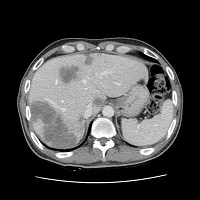

가족성 용종증 이미지

[가족성 용종증]